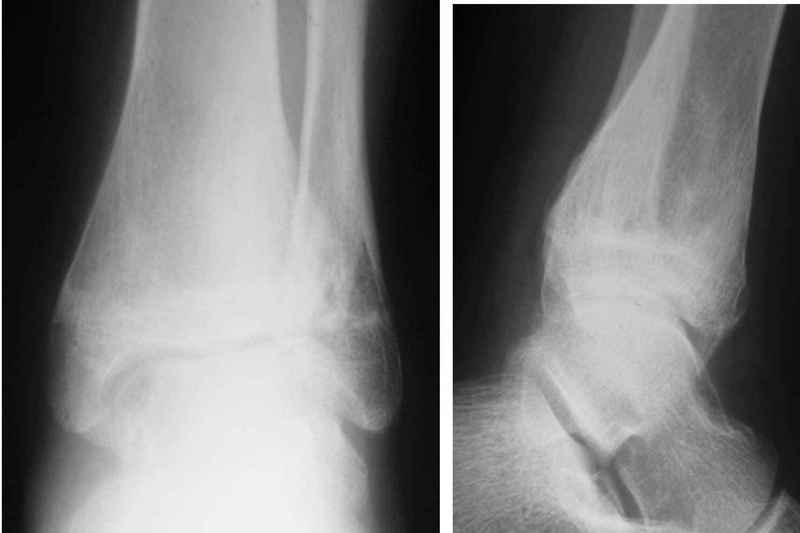

Здравствуйте, коллеги.Обратились родители мальчика 15 лет. Сами врачи.В июле 2009 года - перелом лодыжек.

Лечили спорно, на мой взгляд. В результате - - сращение наружной лодыжки с укорочением, подвывих голеностопа кнаружи (вальгус) в итоге компенсаторно передний отдел стопы ставит на варус. Нагрузку ограничивает.

Снимки в приложении.

С этой целью предлагаем восстановить анатомию м/берцовой кости, следствием чего будет возможность выставить центр тарана по оси голени, устранить эквинус и суппинацию переднего отдела стопы.